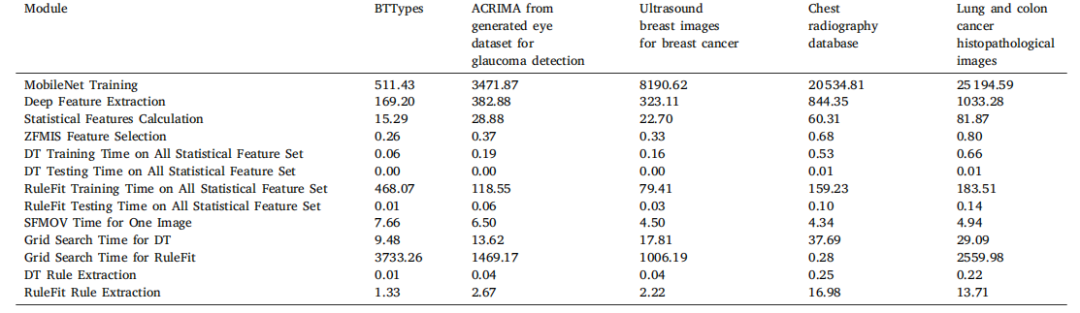

Table 15Computation time (in Seconds) for different modules on multiple datasets

表15 多个数据集上不同模块的计算时间(单位:秒)。